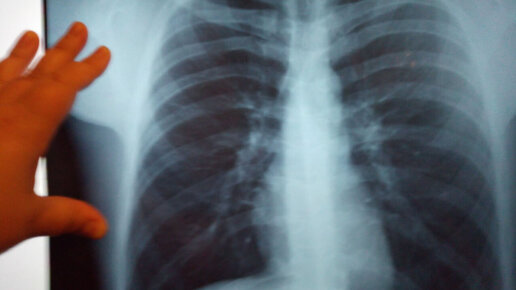

Как выглядят здоровые легкие на рентгене

Рентген является точным и доступным методом диагностики легких, не требующим вторжения в организм. Рентгенографию легких проводят как при заболеваниях (травме легких, опухоли, бронхите, воспалении), так и с целью профилактики при ежегодных медицинских обследованиях. Заболевания легких сначала могут протекать бессимптомно, со временем возможно проявление некоторых симптомов. Если в течении некоторого времени сохраняется кашель, хрипы, появляется боль в грудной клетке, слабость, потливость, кровохарканье, то нужно срочно обратиться к врачу...